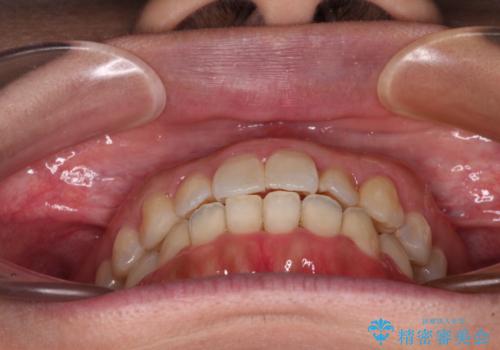

- 前歯の捻れを気にして来院された患者様です。

上顎前歯が捻れて前方に飛び出しており、下顎前歯もそれに沿うようにデコボコとなっていました。

IPR(歯と歯の間を削る処置)によりスペースを獲得して上下前歯のデコボコを改善し、インビザラインにて矯正治療を行うこととしました。

捻れていた前歯の形態が、先端が欠けていたり、一部むし歯処置により左右非対称の形態となっていたため、なかなかゴールが定まらず、治療期間がかかってしまいました。